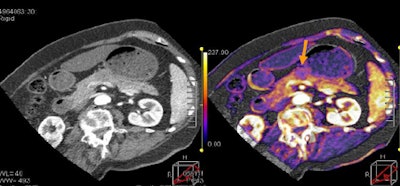

| Tumor and pancreas head are visible on tumor map, with PET image for comparison. All images courtesy of Dr. Sonja Kandel. |